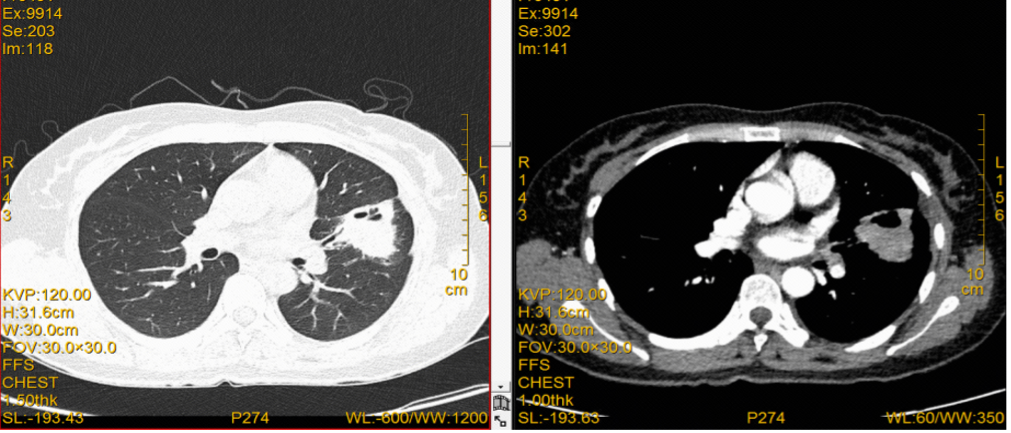

肺部病灶:一线阿美替尼联合化疗治疗6周疗效就达到PR,患者持续用药至今(2022.12),肺部疗效仍为PR。

图4:治疗期间胸部CT检查